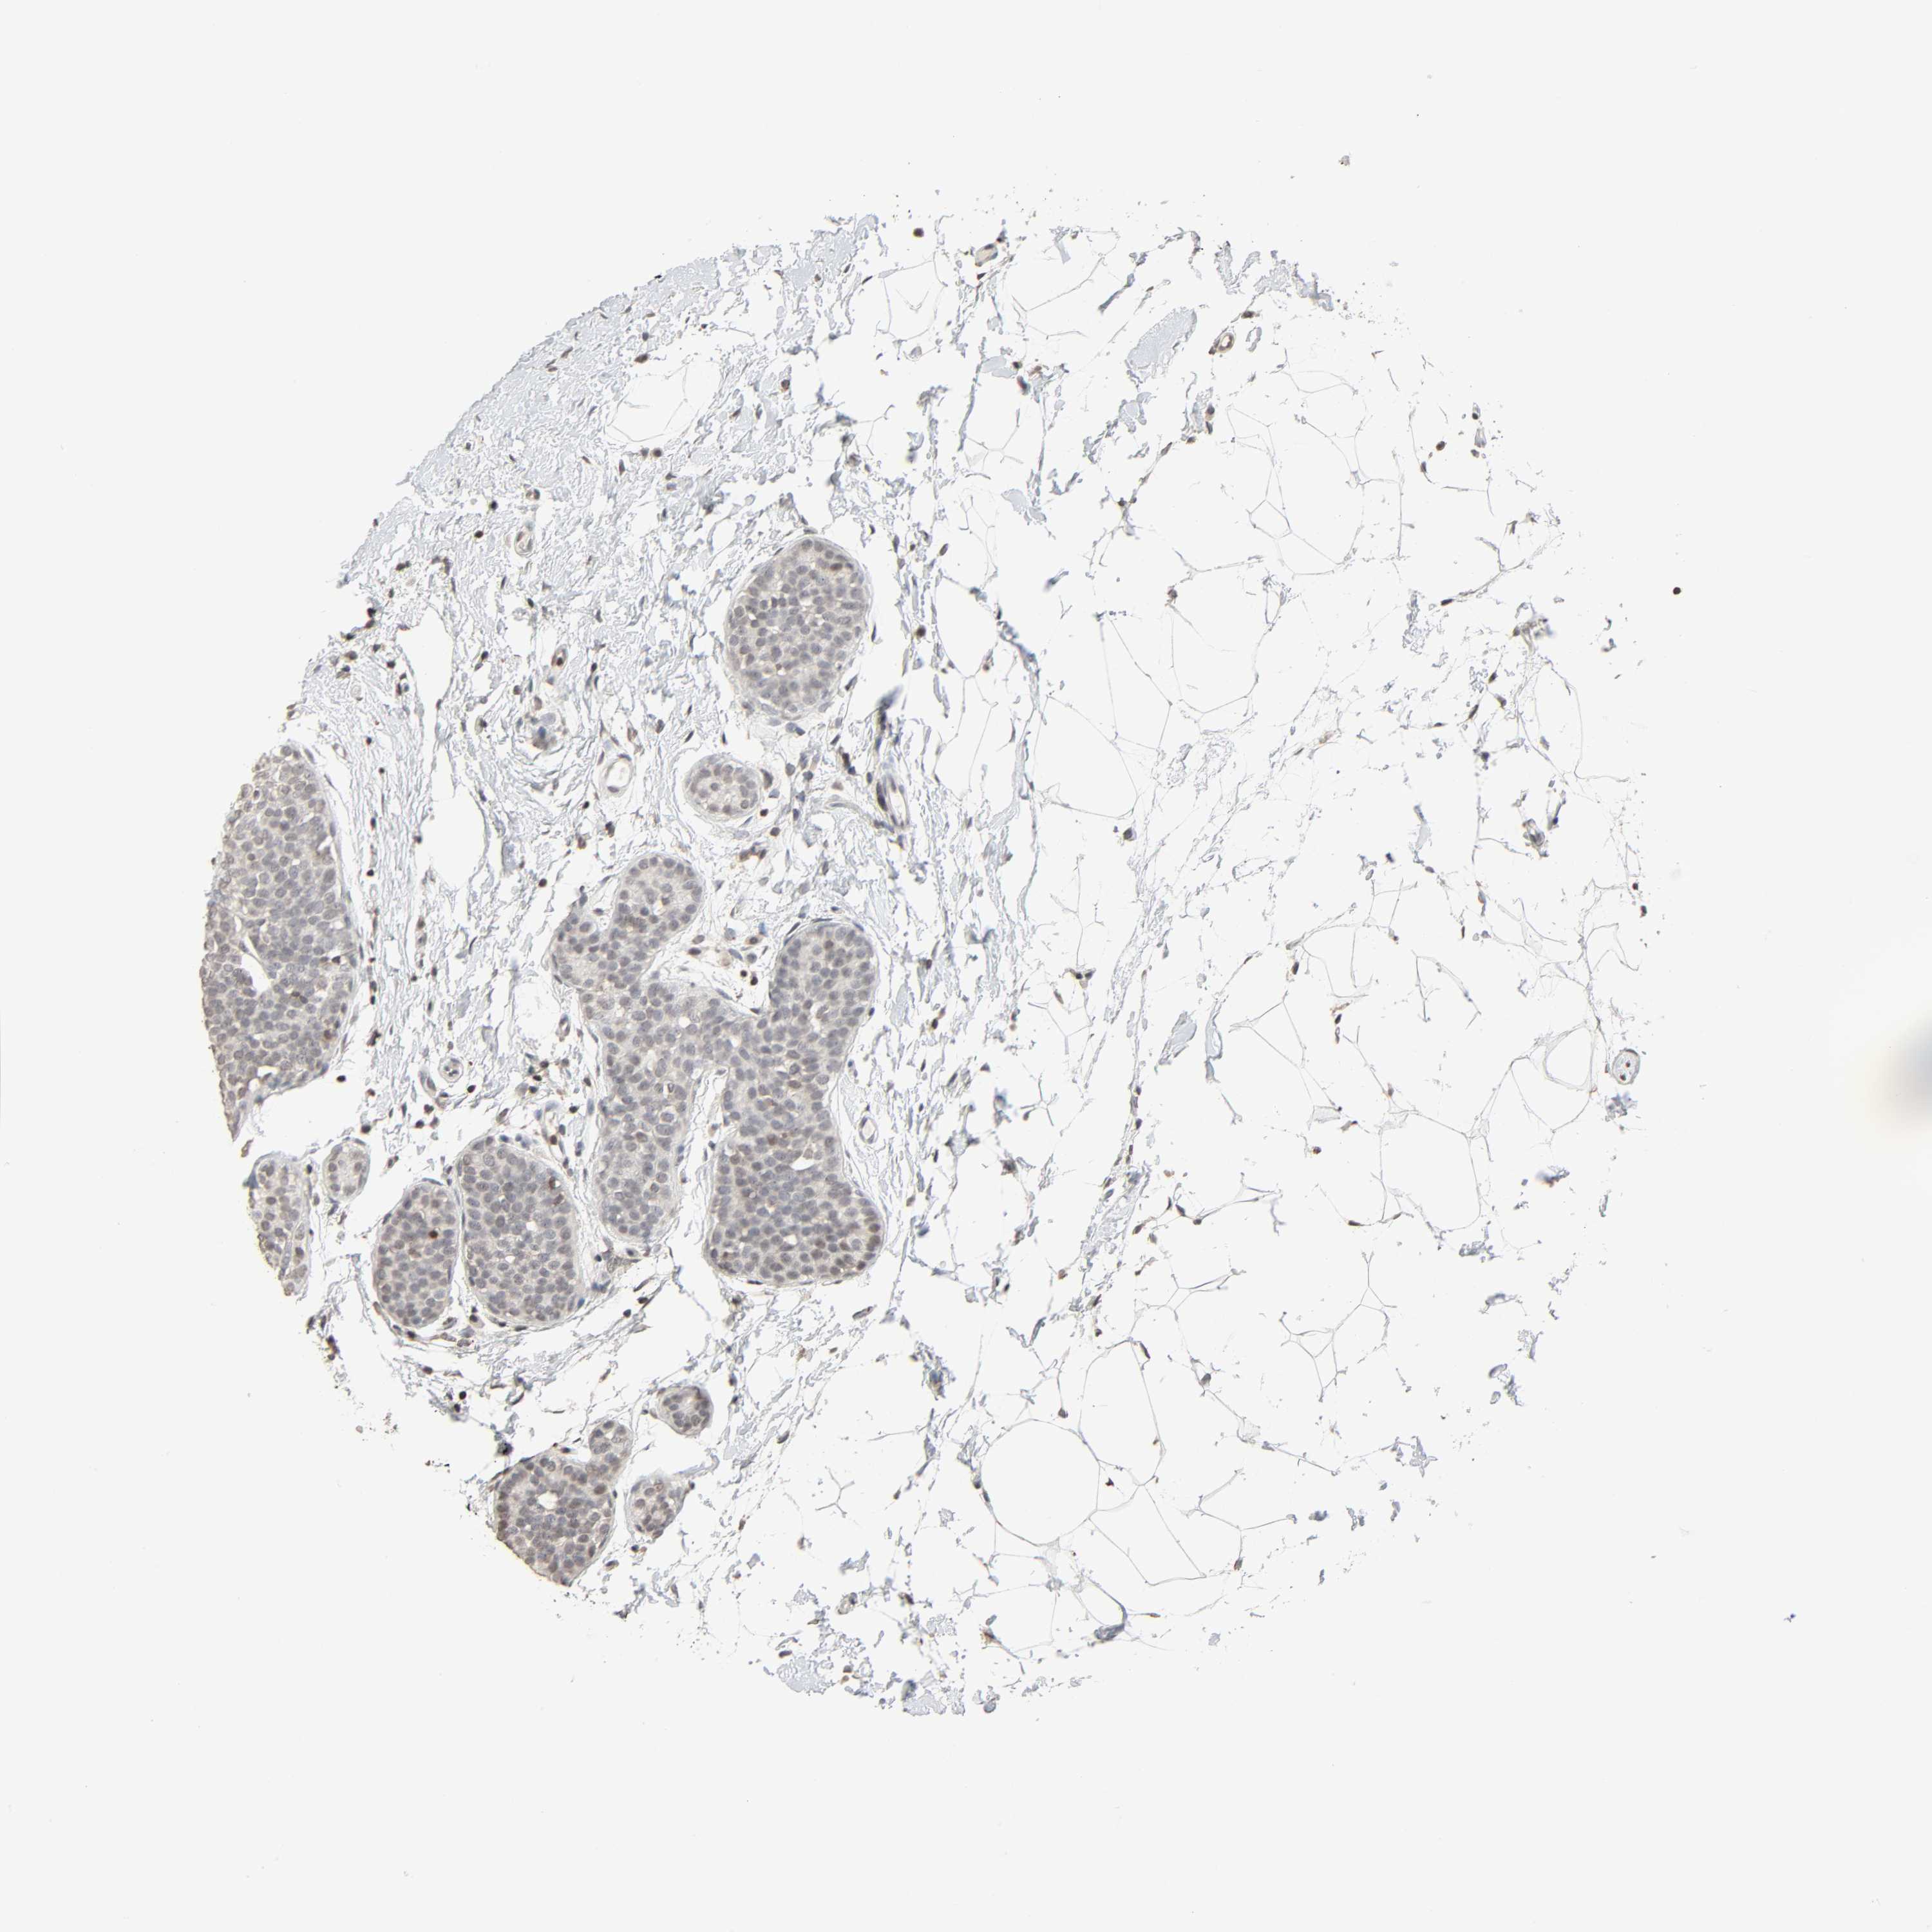

BRCA TCGA BRCA VALIDATION PROTEIN EXPRESSION